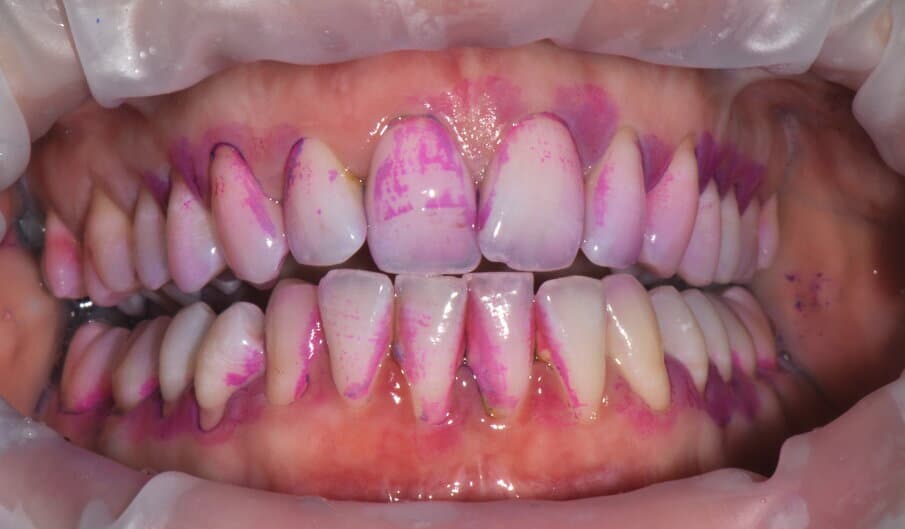

- 2Valutazione del Sanguinamento: l'indice di sanguinamento è un indicatore diretto di infiammazione attiva

Il primo passo è fondamentale: il paziente deve diventare un alleato attivo. Spieghiamo la natura della malattia, insegniamo le corrette tecniche di spazzolamento e uso del filo interdentale, rimuoviamo il biofilm sopragengivale e affrontiamo i fattori di rischio modificabili come fumo e diabete.